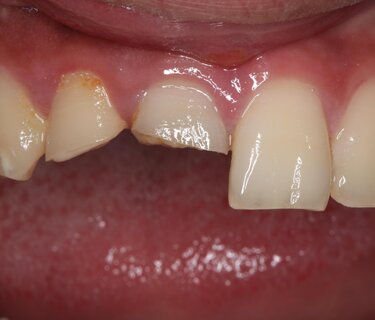

Figure 1: Blunt force trauma fractured and chipped this 19-year-old patient’s anterior teeth #7 and #8, which were repaired in single visit.

This case showcases how a trauma patient can be treated immediately in a single visit. This 19-year-old male presented to my practice with severely fractured teeth #7 and #8 (Figure 1) as a result of being assaulted. Unfortunately, he had waited 48 hours before seeking treatment and the exposed pulp required us to perform root canals on both anterior teeth with core buildups to retain the crowns (Figure 2).  The teeth were prepped and the preps scanned for import into CAD design software (ChairsideCAD, Exocad) (Figures 3 and 4). Two full-contour crowns in shade A2 (IPS e.max CAD, Ivoclar Vivadent) were milled, then crystalized, stained, glazed and placed in the mouth (Figure 5). One year later the patient returned for a post-op appointment to ensure the success of the root canal procedure and that the margins had filled in nicely with no inflammation (Figures 6 and 7).